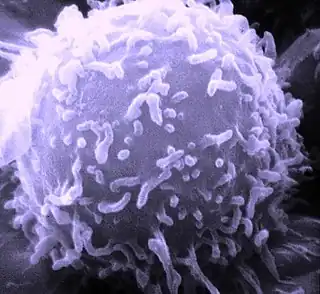

Los linfocitos son células del sistema inmunitario. Son un tipo de leucocito que provienen de la diferenciación linfoide de las células madre hematopoyéticas ubicadas en la médula ósea y que completan su desarrollo en los órganos linfoides primarios y secundarios (médula ósea, timo, bazo, ganglios linfáticos y tejidos linfoides asociados a las mucosas). Los linfocitos circulan por todo el organismo a través del aparato circulatorio y el sistema linfático.[1][2]

Son los leucocitos de menor tamaño (entre 9 y 18 μm), y representan aproximadamente el 30 % (del 20 a 40 %) del total en la sangre periférica. Su morfología es variable, de acuerdo con la cual se clasifican en linfoblastos, prolinfocitos y linfocitos propiamente tal, ya sea inactivos o activados (como los plasmocitos). Presentan un gran núcleo esférico que se tiñe de violeta-azul y la cantidad de citoplasma varía entre escaso (situación más frecuente, en la cual el citoplasma se observa como un anillo periférico de color azul) a abundante. En el citoplasma se encuentran algunas mitocondrias, ribosomas libres y un pequeño aparato de Golgi.[2]